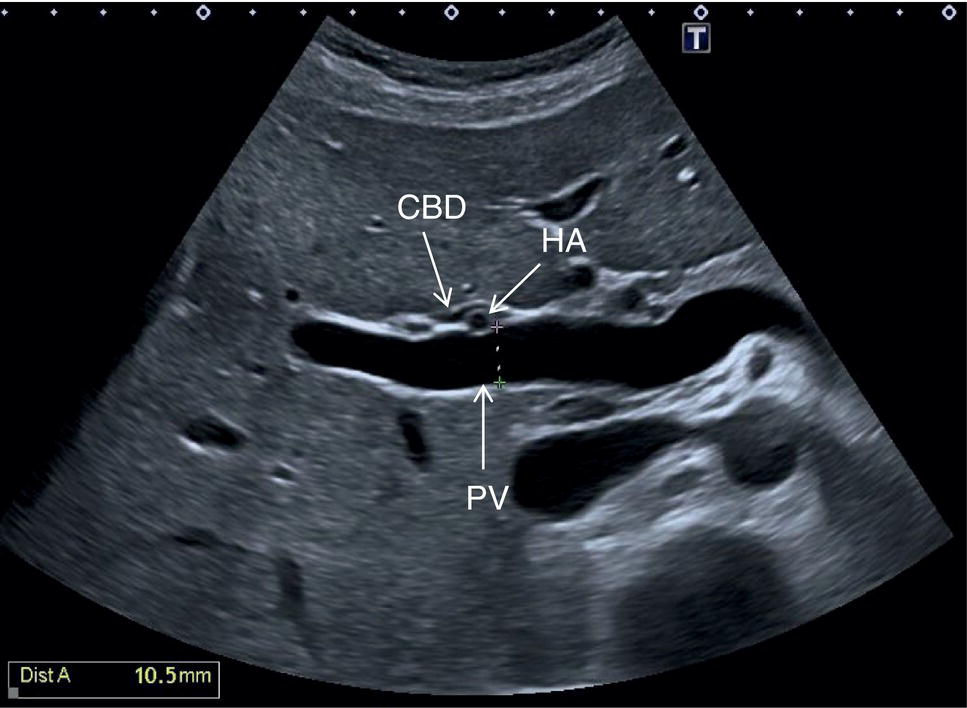

The PV calibre is measured at the hepatic hilum at the crossing with the HA, where a diameter up to 12.5–13 mm is considered normal (Figure 3.34).

The HA has echogenic walls, it runs anteriorly to the PV and posteriorly to the CBD, and its normal calibre at the hepatic hilum measures up to 3 mm in diameter (Figure 3.34). The hepatic veins have thinner and less echogenic walls [8] and have a straighter and linear course compared to the portal venous system. Although the measurement of the hepatic veins is usually not performed on a routine basis, the cut‐off value of their calibre is approximately 8 mm, measured at about 2–3 cm from their confluence into the IVC [9]. It should be kept in mind that in lean subjects both IVC and hepatic veins may be more ectatic. When performing a liver ultrasound scan it is important to keep in mind that the echogenicity of both hepatic veins and PV walls changes according to the angle between the ultrasound beam and the vascular wall. The more acute is the angle of insonation, the closer it is to being parallel to the longitudinal axis of the vessel. Therefore, despite there being clear differences between the thick perivascular collagen of the portal venous system and the thin walls of the hepatic veins (Figure 3.35), if the angle of insonation is low between the ultrasound beam and the PV walls, these could appear very thin or even not be visible. On the other hand, if the angle of insonation with the hepatic veins is close to 90°, the walls will appear thick and echogenic. It is always important to keep in mind this physical principle, remembering the anatomical landmarks and tracing the vessels to their origin: the PV to the hepatic hilum and the hepatic veins to their confluence into the IVC.

In normal physiological conditions, the CBD is the only biliary duct that can be clearly seen as a thin tubular structure with echogenic walls that in the majority of cases runs anteriorly and parallel to the PV at the level of the hepatic hilum (Figure 3.8). However, the anatomical relationship of the biliary ducts and the portal vessels may vary along their course, and usually the peripheral biliary ducts (which are only clearly visible when dilated or significantly thickened) run posteriorly to the PV (Figures 3.9 and 3.10).

The CBD measures between a minimum of 2–3 mm and an upper limit of 6–7 mm. Larger calibres are observed, especially post cholecystectomy and with age, where it is generally accepted that the calibre may increase by 1 mm each decade after 70 years [3].